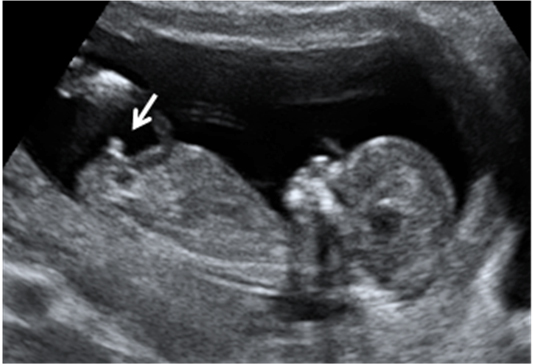

En la semana 12 de gestación, la embarazada aún no nota los movimientos del bebé que crece dentro de su útero. Pero en esta ecografía en 4D se observa sus vigorosos movimientos.

La curiosa ecografía de este feto de 12 semanas comienza con la imagen de espaldas. El niño se gira hasta colocarse de perfil y es entonces cuando empieza a mover brazos y piernas con agilidad. Todo un signo de bienestar fetal.